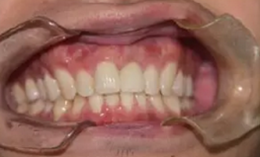

永久修復(fù)

永久修復(fù)后3年進(jìn)行回訪,種植體骨結(jié)合穩(wěn)定,美學(xué)效果良好。

圖14 永久修復(fù)3年后的回訪